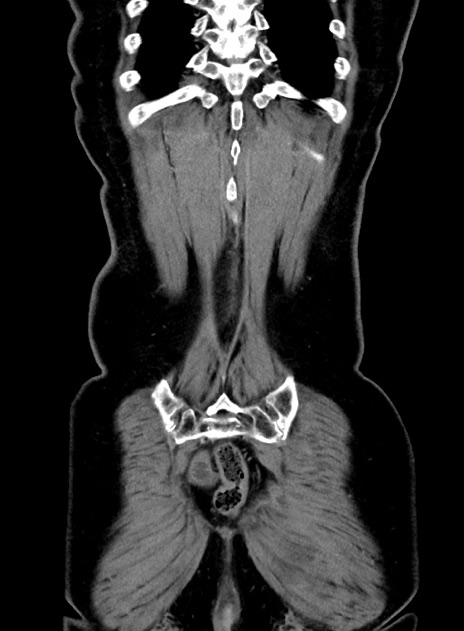

症例9(冠状断像)

【症例】 60歳代女性

【主訴】むかつき、みぞおちの痛み

【現病歴】3日前よりむかつきがあり、食事がとれない。

【既往歴】糖尿病

【身体所見】発熱なし、心窩部圧痛軽度あるも、腹膜刺激症状なし。

【データ】WBC 7400、CRP 1.92